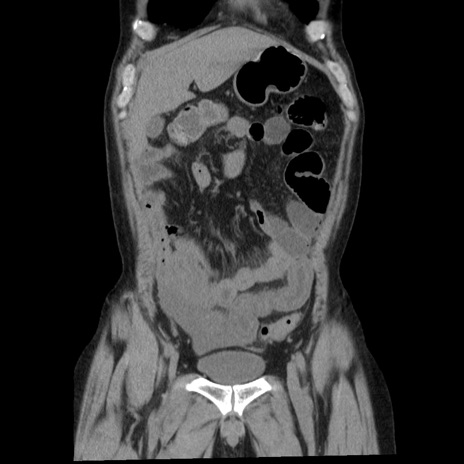

症例29(冠状断像)

【症例】40歳代男性

【現病歴】2日前から胃痛あり。徐々に周期的な激痛に変化した。本日になっても激痛があるため受診。

【身体所見】意識清明、BT 38-39℃台あり、腹部:膨満、やや硬、右下腹部に圧痛あり。

【データ】WBC 8500、CRP 23.26